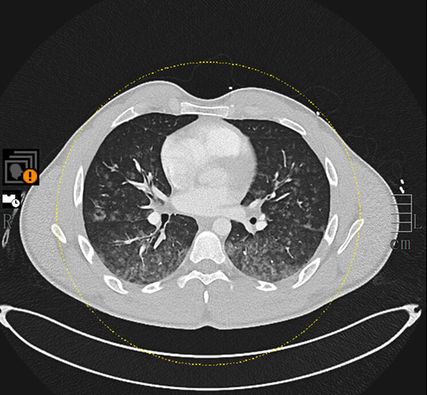

Während des stationären Aufenthaltes hatte der junge Patient keinen neuerlichen blutigen Auswurf. Vor einer geplanten Bronchoskopie mit Biopsie erfolgte eine neuerliche Thorax-CT, wobei sämtliche Konsolidierungen vollständig rückläufig waren (Abb. 2). Mögliche Differenzialdiagnosen waren an diesem Punkt entweder ausgeschlossen oder erschienen als sehr unwahrscheinlich. Es musste daher eine andere Genese geben.